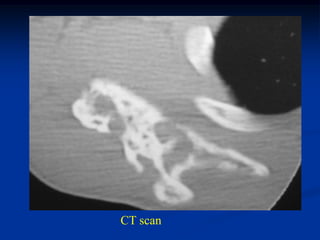

Axial CT scan